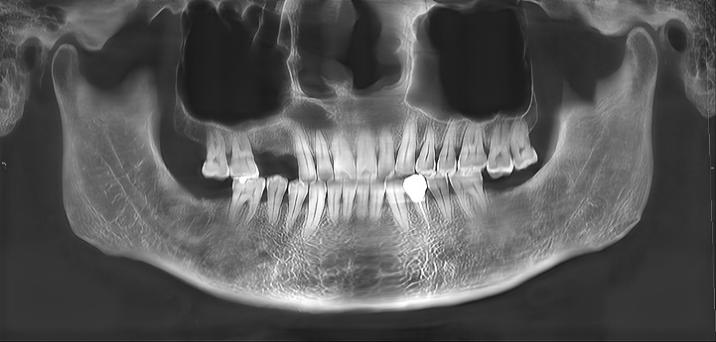

一周后,老赵的创口就愈合了。三个月后复查的结果更是喜人:两个囊肿被完整切除,没有复发的迹象;上颌窦口完整保留,骨腔修复正常。最关键的是,由于手术是从口腔内进行的,所以面部没有任何疤痕。老赵连连感叹:“这技术真厉害,两个囊肿一次就解决了,脸上还一点痕迹都没有。”

术后 3 个月复查